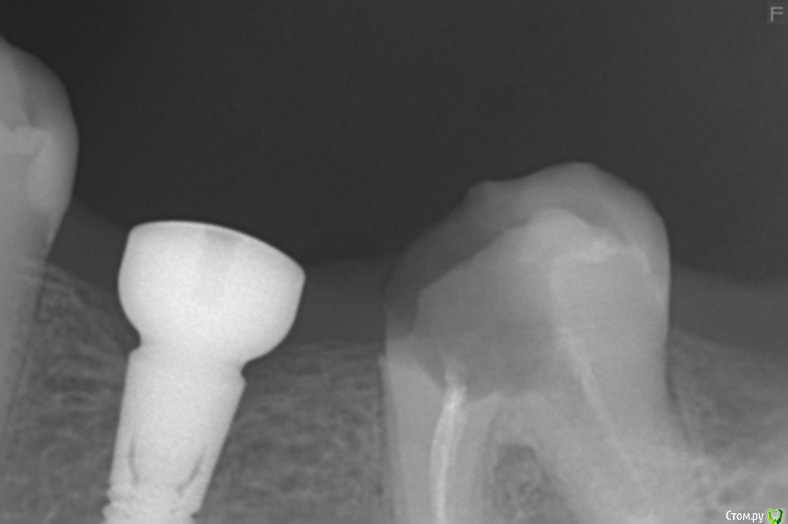

Dmitriy_ Опубликовано 2 февраля, 2017 Поделиться Опубликовано 2 февраля, 2017 Доброго дня уважаемые врачи! Протезируете или удаляете такие зубы?Так получилось что лечение (клиника1) и протезирование+имплантация (клиника2) делаю в разных местах, произошла некоторая несогласованность действий. Коронка в проблемном месте ниже уровня десны, до кости в одном месте доходит. Хирургическое удлинение коронки в клинике2 делать отказались из-за рядом стоящего импланта, т.е. этот вариант как я понял не обсуждается. Но протезировать могут, спросил можно ли добиться герметичности, ответ положительный, сложно но можно. Но прогноз сделать сложно. Мне не хотелось бы возвращаться к этому вопросу года через 3, плюс лечение не дешевое. Спасибо! Ссылка на комментарий

Доктор Добрых Дел Опубликовано 3 февраля, 2017 Поделиться Опубликовано 3 февраля, 2017 Однозначно удаление и имплантация. И дело не в герметичности прилегания будущей коронки а в том что в том месте под десной где будет искусственная коронка должны быть ткани зуба к которым прикрепляется десна. Так как там будет инородное тело, то прикрепления десны не будет. Будет хроническое воспаление, которое приведёт к развитию зубодесневого кармана, кариесу корня и в конечном счёте к удалению зуба (из-за убыли кости может пострадать и рядом стоящий имплантат). Ссылка на комментарий